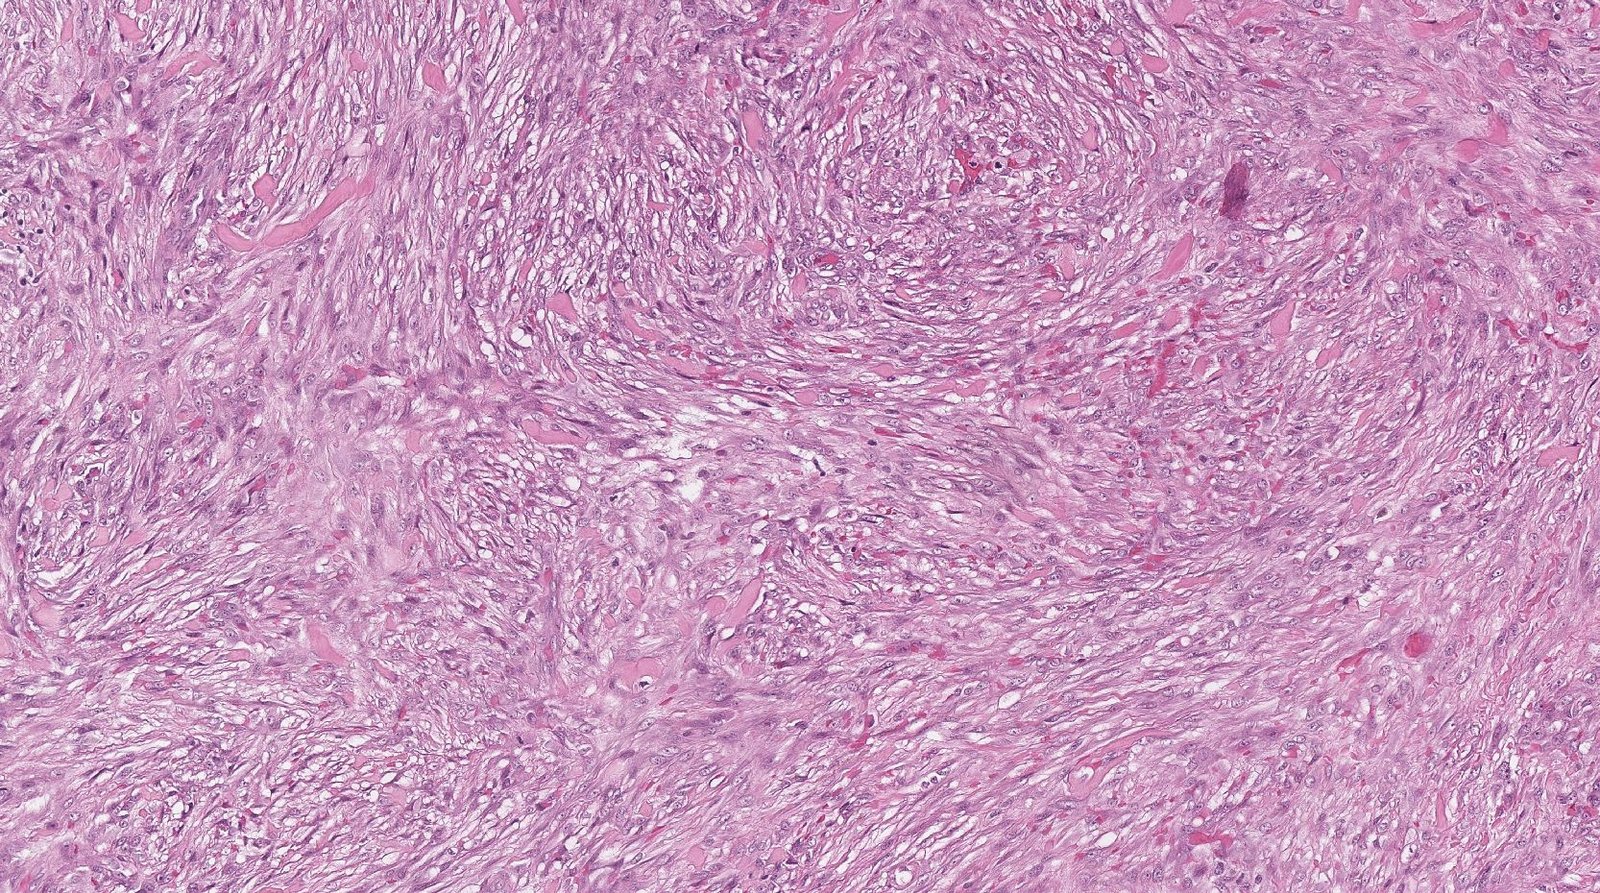

Case: WristMass

Final Diagnosis: